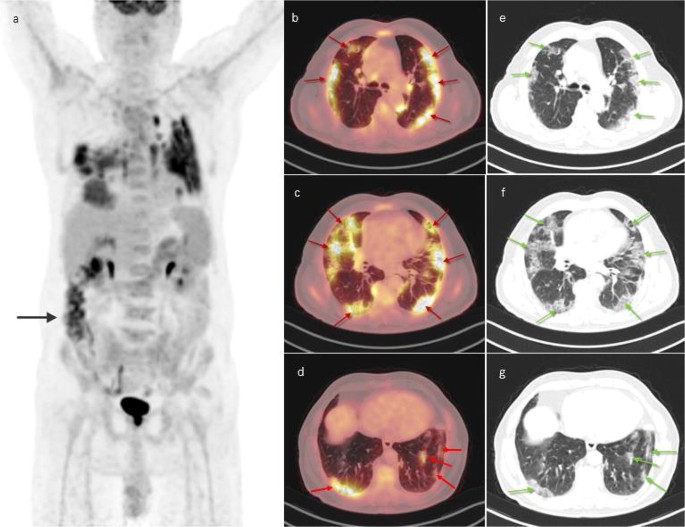

A Case Of Covid 19 Lung Infection First Detected By 18f Fdg Pet Ct Springerlink

link.springer.com